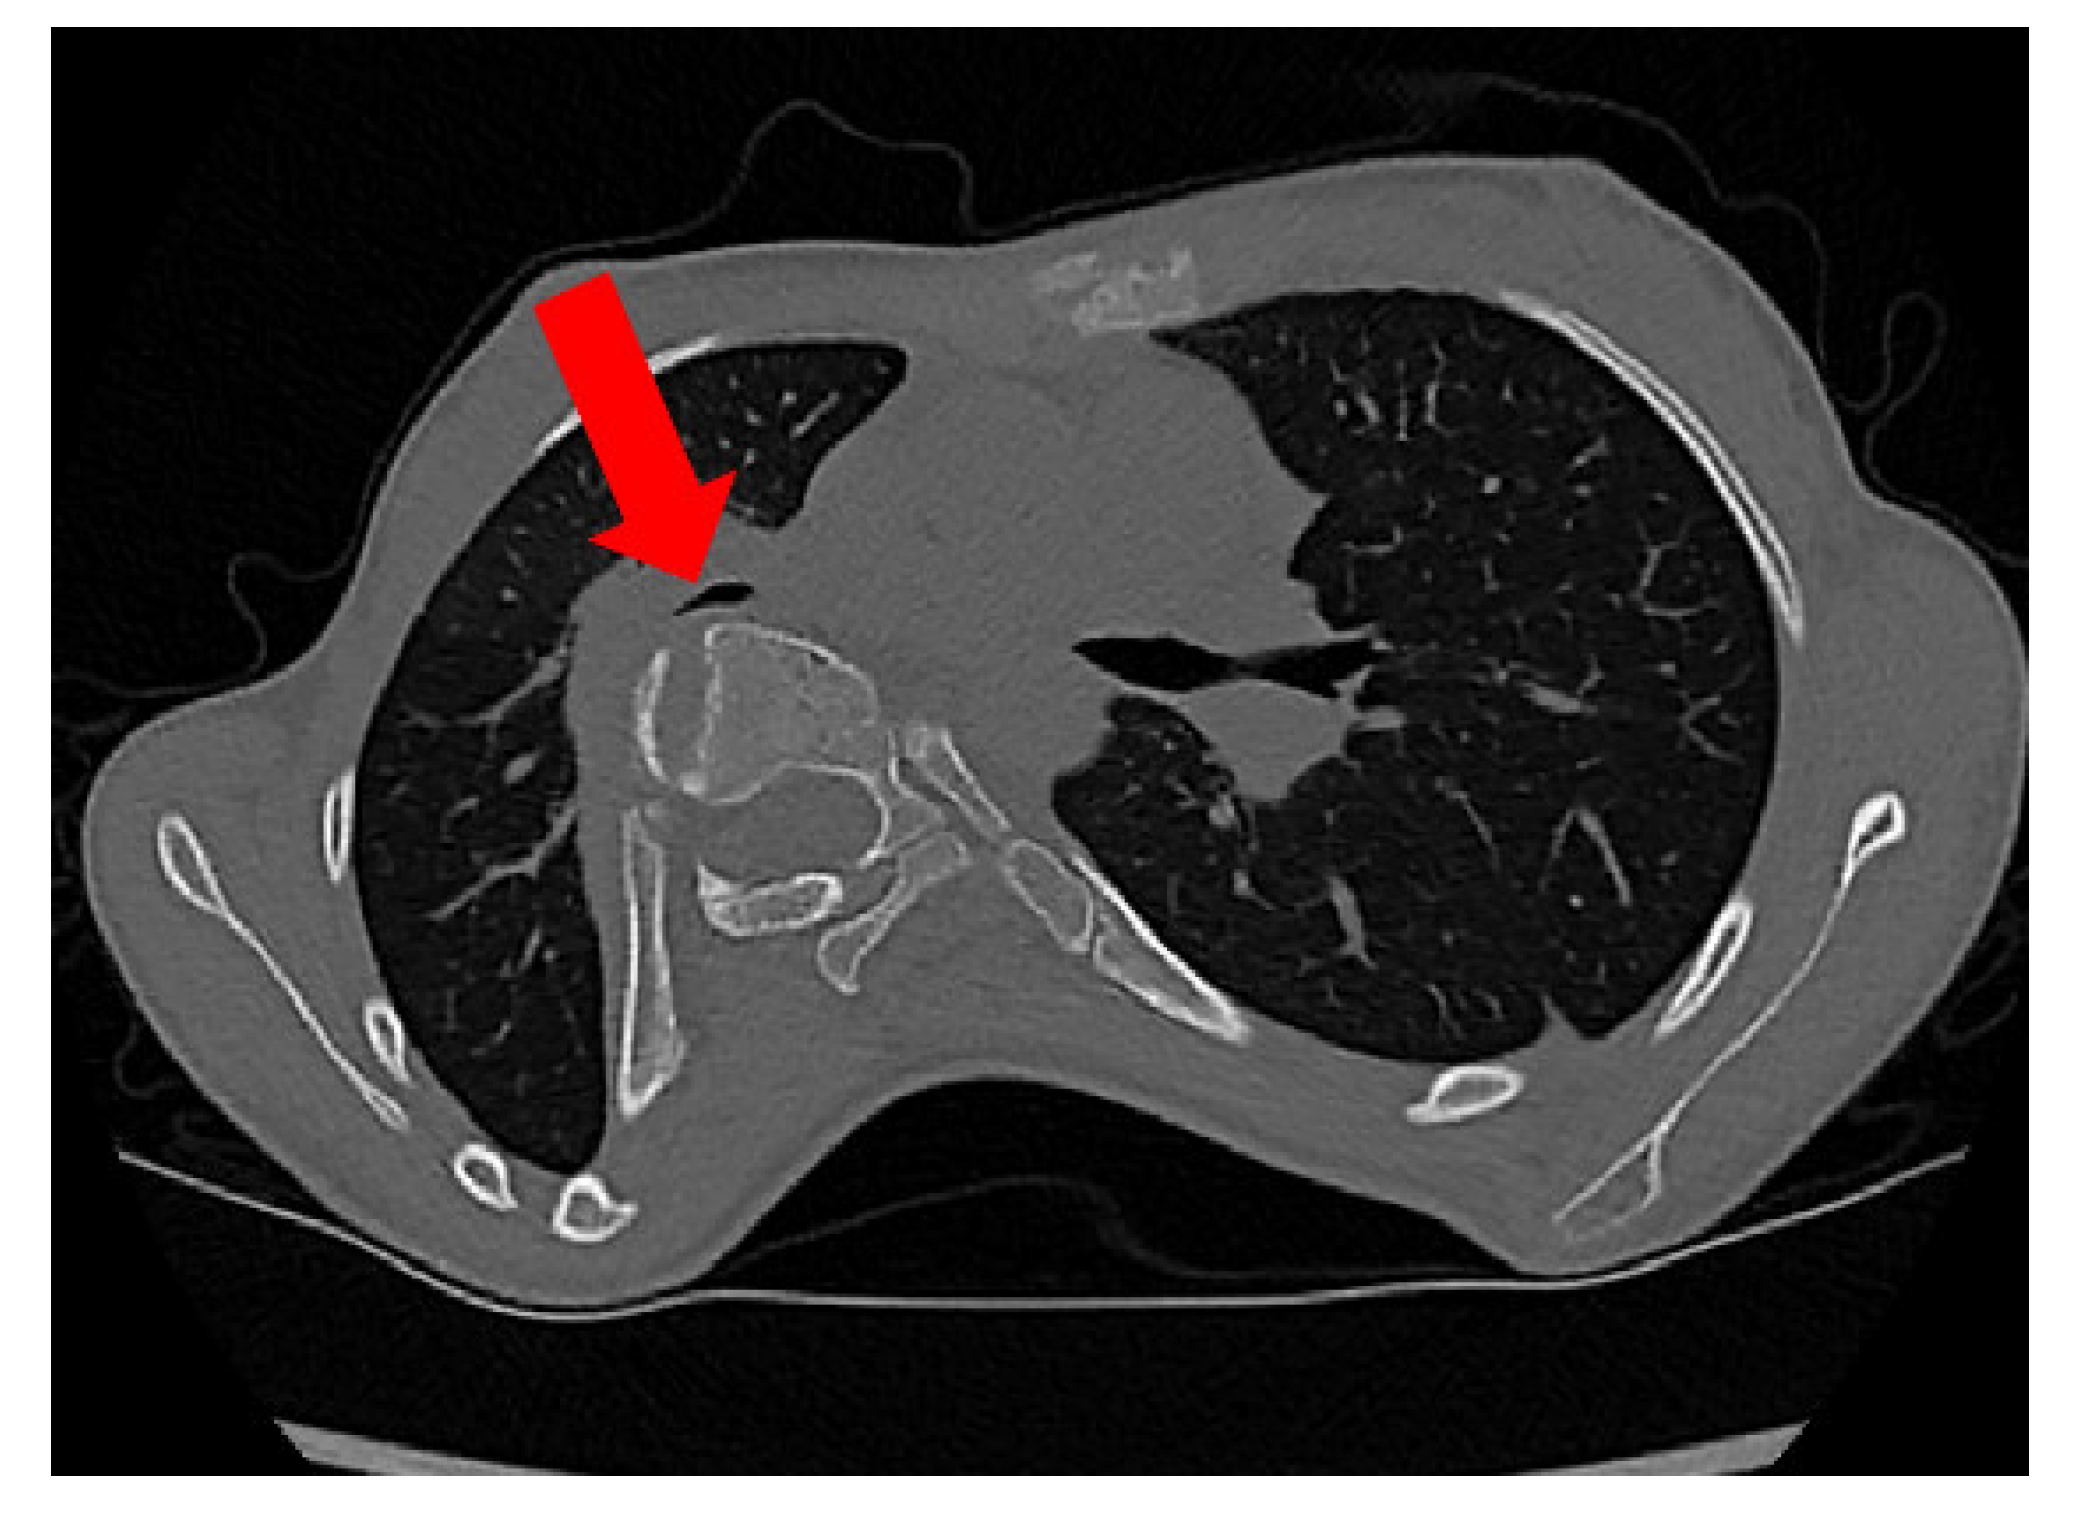

2.3. CT

- Sagittal diameter and sternovertebral distance: These are two parameters for measuring the sagittal depth. The sternovertebral distance is the anterior–posterior distance between the posterior midpoint of the sternum and the anterior point of the apical vertebra [21]. The sagittal diameter is the anterior–posterior distance between the posterior midpoint of the sternum and the anterior point of the foramen. Both are measured on an axial CT scan. Takahashi et al. [22] report a significant negative correlation between the sagittal diameter and spine curvature. Measurements of the sagittal depth have been used to evaluate pre- to postoperative differences [21]. It has been shown that the sagittal diameter, as well as the sternovertebral distance, significantly decreases after spinal fusion surgery [21]. The sagittal diameter has also been used to evaluate the effect of thoracic deformity on pulmonary function [22].

- Spinal intrusion ratio: This parameter represents the sagittal intrusion of the thoracic spine into the chest and has been demonstrated to be related to the size of the airways [5,23]. SIr is the ratio between the distance from the anterior vertebral column contour to the interior contour of the convex ribs and the distance from the internal sternal surface to the anterior contour of the vertebral column.